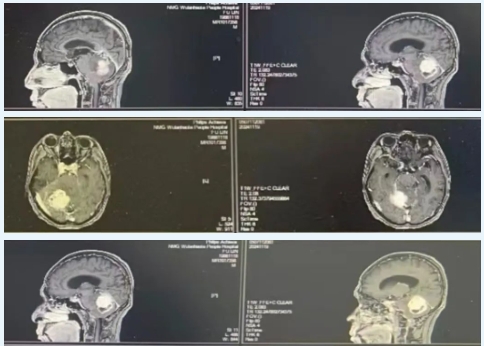

患者福某,来自扎赉特旗,今年58岁。近20多天来,他逐渐出现了头痛、头晕的症状,并且伴有走路不稳的情况。这些症状持续不缓解,让患者及其家人十分担忧。于是,在家人的陪同下到当地医院就诊。经过头颅核磁共振平扫及增强扫描检查,结果显示小脑占位,医生初步判断可能是脑膜瘤,不除外转移瘤等情况,并建议进行手术治疗。

为了进一步确诊和治疗,福某随后转至兴安盟人民医院神经外科门诊。经过神经外科团队的严谨检查和评估,将福某收入院接受治疗。由于肿瘤位置深在,血供丰富,手术难度和风险都相对较大。然而,在神经外科团队的精心准备下,手术于2024年11月22日顺利进行。

针对福某的病情,神经外科团队决定采用经后颅窝旁正中小脑占位切除术。手术在显微镜下进行,由后颅窝旁正中入路进入,精准找到肿瘤组织,并将其完全切除。整个手术过程十分顺利,成功避免了对周围脑组织、血管和神经的损伤。